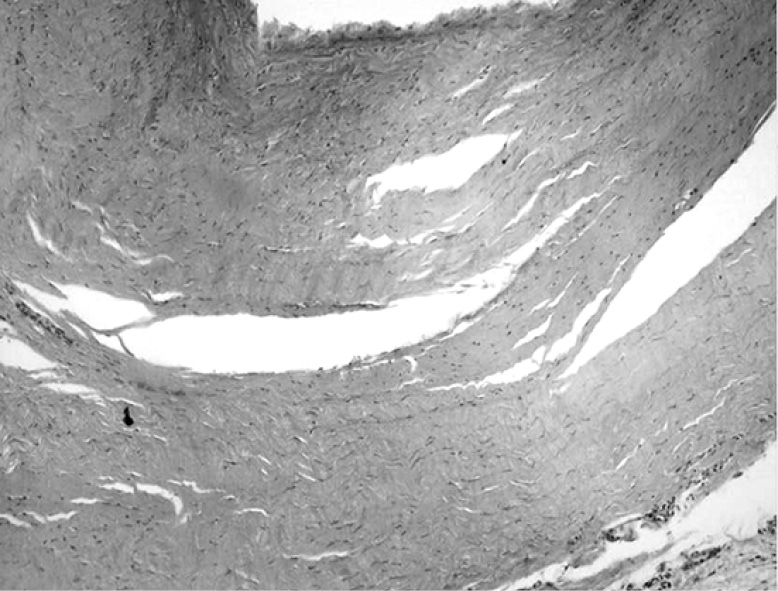

При термической экспозиции в 180 с гистологическое исследование демонстрировало признаки необратимых повреждений, достигающих середины фиброзного слоя стенки кисты (рис. 6). На электронно-микроскопическом уровне определялись признаки глубокой дезорганизации коллагеновых волокон стенки кисты – все коллагеновые волокна потеряли исчерченность и упорядоченность ориентации. Определялись единичные фибробласты с признаками вакуолизации, лишенные отростков и органелл (рис. 7).

Рис. 6. Стенка кисты Бейкера после 180-с нагрева (×400, Г-Э). Термическая деструкция синовиального слоя и глубоко расположенных коллагеновых волокон фиброзного слоя.

Fig. 6. Baker’s cyst wall after 180 s of thermal exposure (×400, G-E). Thermal destruction of the synovial layer and deeply located collagen fibers of the fibrous layer were evident.